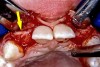

Figure 14a  The information gained from (A) the 3D model was confirmed when (B) the flaps were elevated.

Figure 14a

Figure 14b  The information gained from (A) the 3D model was confirmed when (B) the flaps were elevated.

Figure 14b

Before the day of surgery, the patient was seen by the orthodontist for the removal of the orthodontic brackets. The patient still was not pleased with the position of the two centrals, and it was determined that this would be addressed after implant placement (Figure 13A). The anatomical variations of the crestal tissue and lack of interdental papilla can be appreciated in the close-up views of the right and left sites (Figure 13B and 13C). There were no surprises on the day of surgery as all of the decisions were made during the planning phase, before the scalpel ever touched the patient. The occlusal view of the CT 3D model revealed the wider alveolar ridge on the right side and thinner crest on the left side (Figure 14A). This was confirmed when the full thickness mucoperiosteal flaps were elevated, and the underyling bone revealed (Figure 14B). The tooth-borne templates were designed to facilitate the drills and drilling sequence specific to the diameters of the predetermined implants (Figure 15A). Each template contained an embedded 5-mm long stainless steel tube, which was approximately 0.2-mm wider than each drill (just wide enough to allow for the drills to rotate freely). Once positioned over the natural teeth, the template was secure and offered precision accuracy in transferring the implant locations from the original software-designed plan, allowing the potential for internal and external irrigation (Figure 15B). The 3.7-mm diameter Tapered Screw-Vent implant drilling sequence requires three drills: pilot, intermediate, and final sizing. Thus, three separate templates were fabricated to a.commodate these sizes. The templates were removed easily and replaced with the next sequential size in less time than it takes to change the drill on the surgical handpiece. After the osteotomies had been.completed, the implants were delivered to the site (Figure 16A and Figure 16B). For this internal hex connection implant, the author r.commends that the flat of the antirotational hex be positioned to the facial for proper orientation of the restorative.components (Figure 17A). Preprepared margins were created from a milled titanium fixture mount transfer post, which was delivered to the implant as support for an immediate transitional restoration. The facial “dot” helped confirm the orientation of the abutment to the facially positioned flat side of the internal hex connection (Figure 17B). Before cementation of the transitional acrylic restorations, a closed-tray, fixture-level impression was made, and a soft-tissue model fabricated.